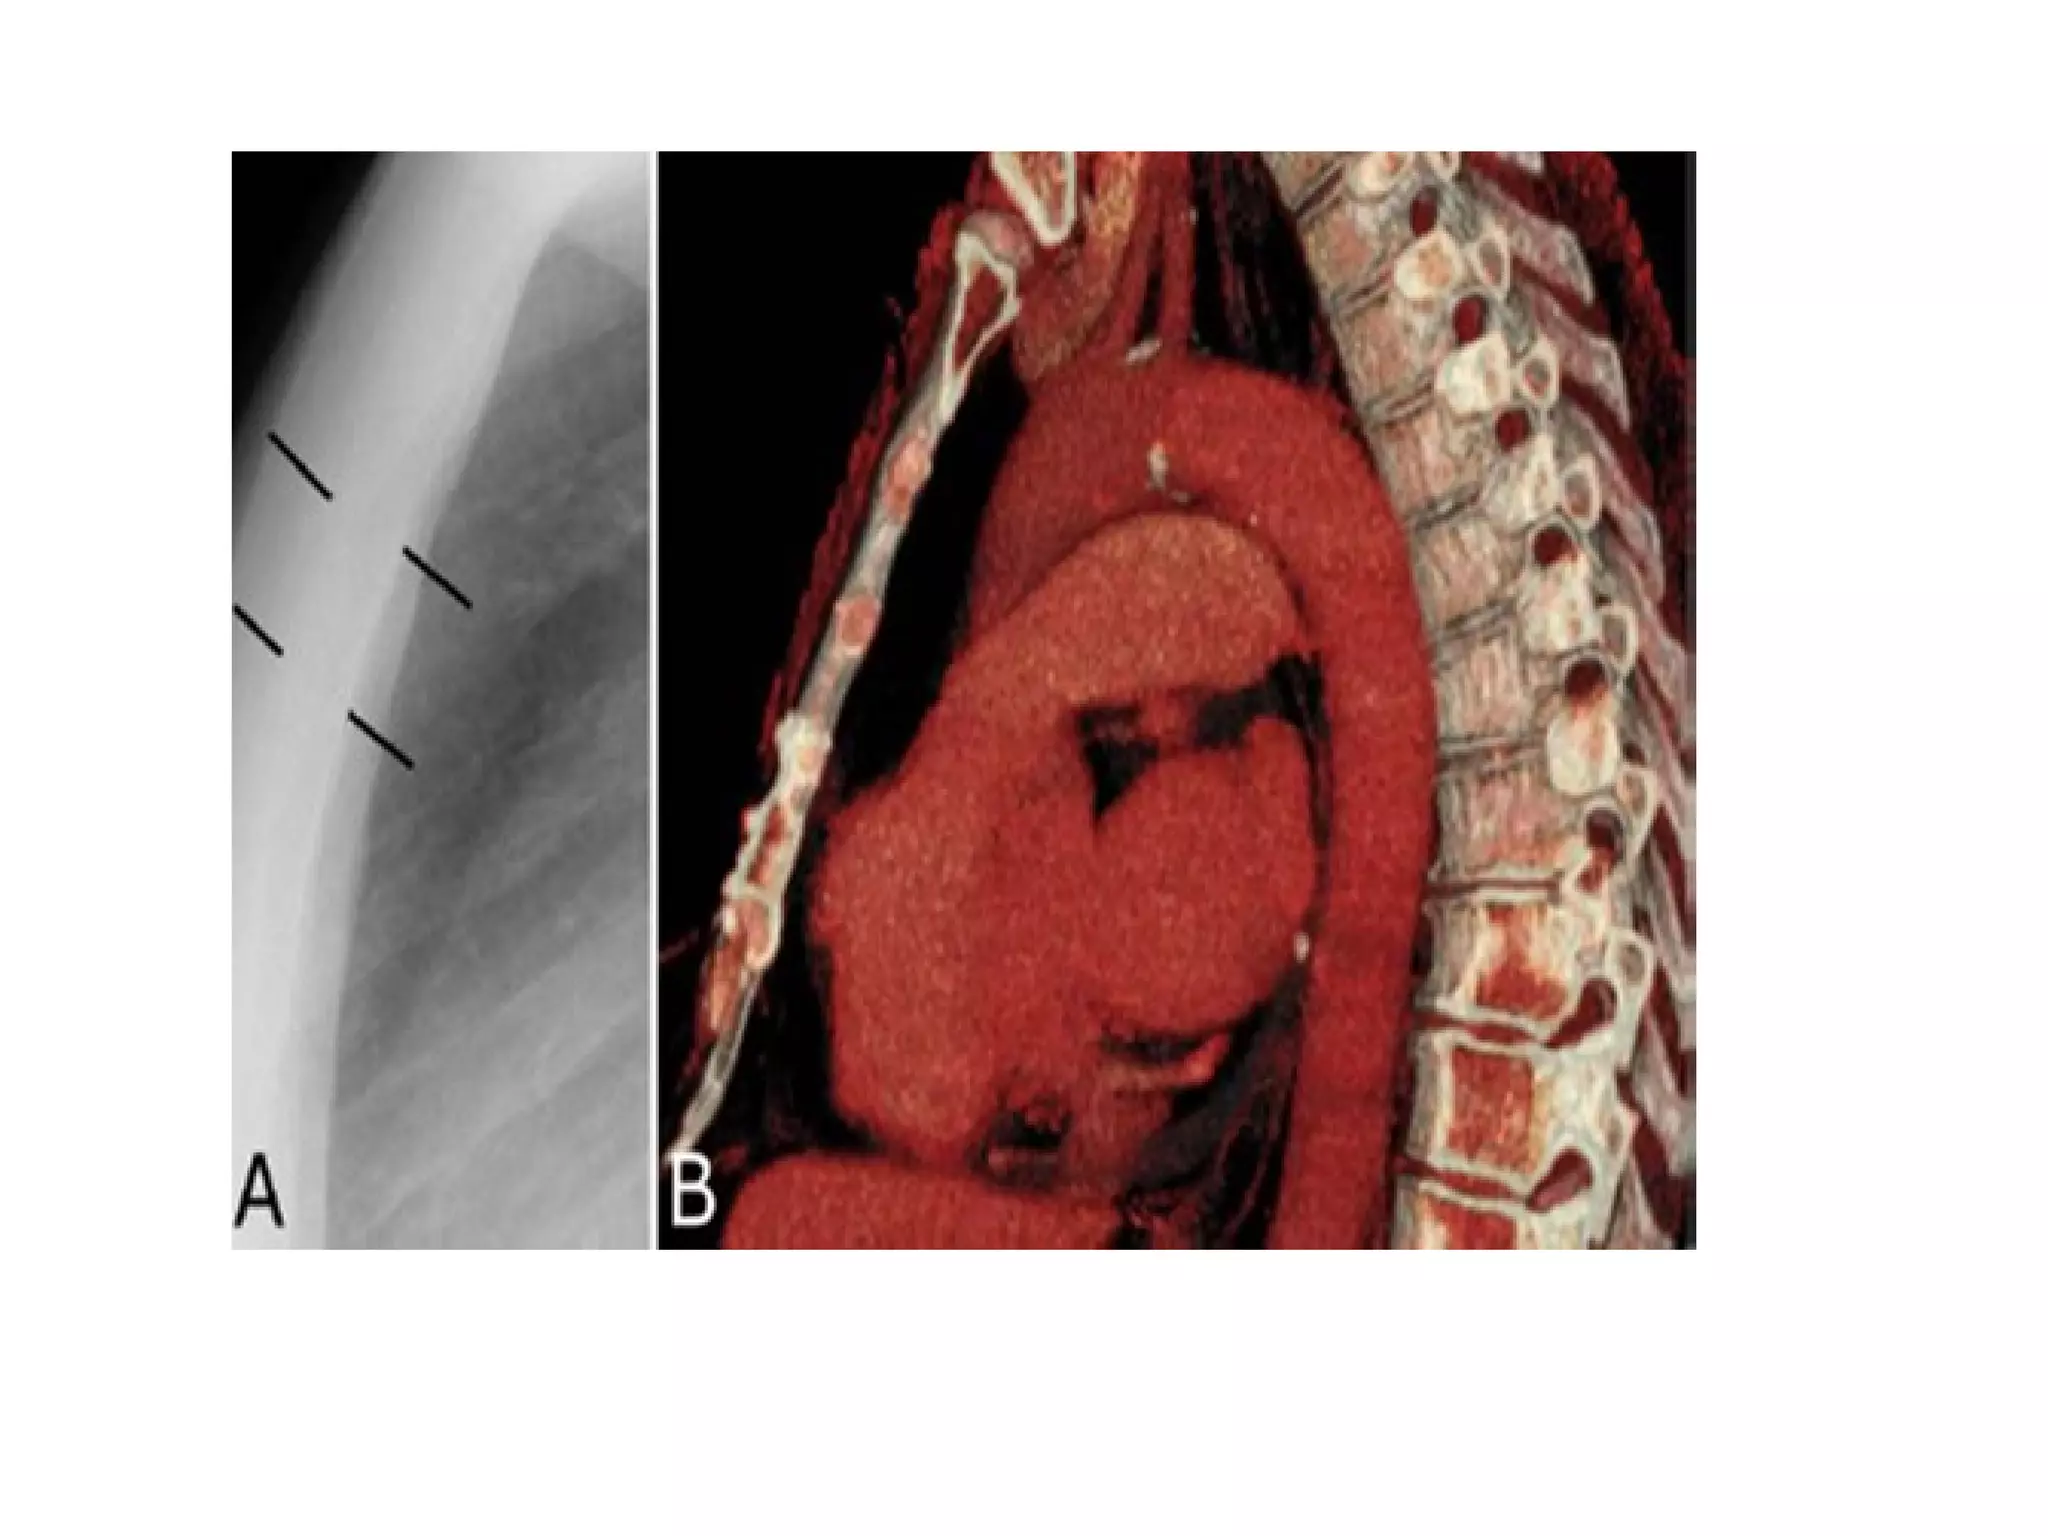

The fissures

The main fissures

The horizontal fissure is seen often incompletely

on PA film

The oblique fissures are seen on lateral film

commence posteriorly at the level of T4 or T5

passing through the hilum. The left is steeper

and finishes 5cm behind the anterior

costophrenic angle, where as the right ends just

behind the angle.

The fissures The mainfissures The horizontal fissure is seen often incompletely on PA film The oblique fissures are seen on lateral film commence posteriorly at the level of T4 or T5 passing through the hilum. The left is steeper and finishes 5cm behind the anterior costophrenic angle, where as the right ends just behind the angle. Accessory fissures, the azygos fissure is comma shaped and nearly always right sided.